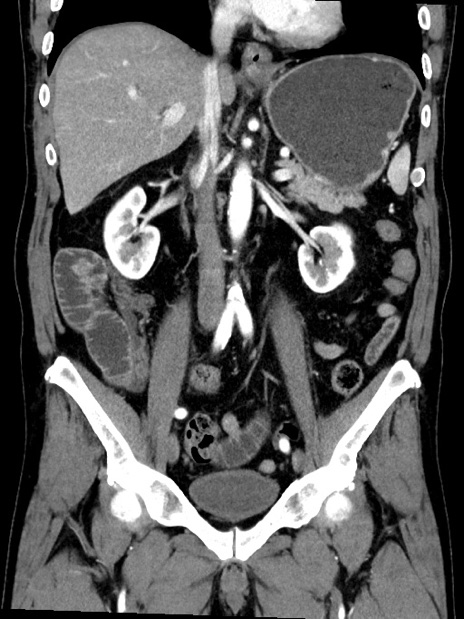

症例35(冠状断像)

【症例】70歳代 男性

【主訴】腹部膨満、嘔吐

【現病歴】昨日より腹部膨満感出現。本日増悪し、仙痛出現。嘔吐あり、受診。

【既往歴】糖尿病、胆摘後

【身体所見】BP 149/80mmHg、HR 74/min、BT 35.9℃、腹部:膨満、軟、圧痛なし。腸雑音減弱あり。上腹部正中切開瘢痕あり。

【データ】WBC 13500、CRP 1.72